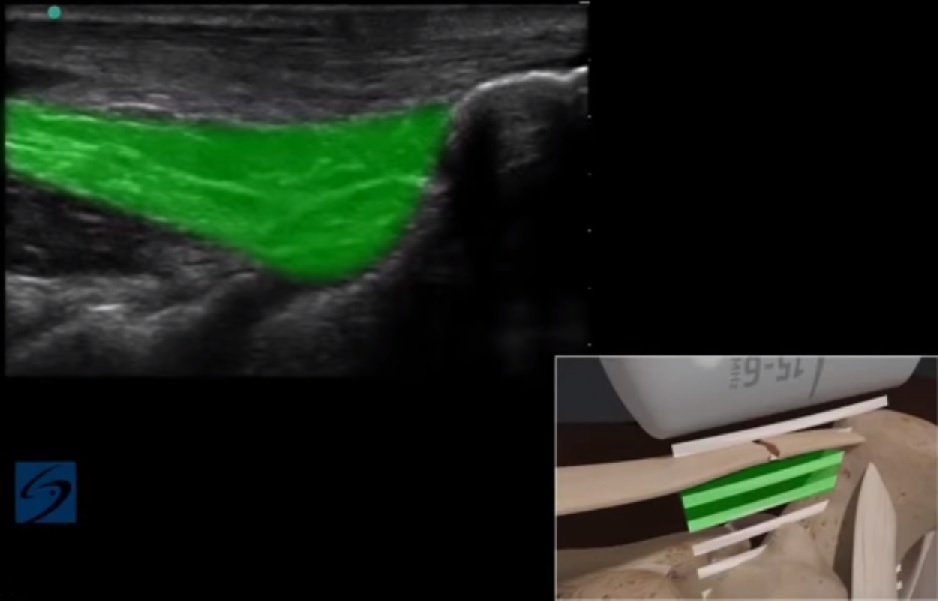

Bild: Fuß und Sprunggelenk, Kager'scher Fettkörper

Markierter Bereich: Kager'scher Fettkörper